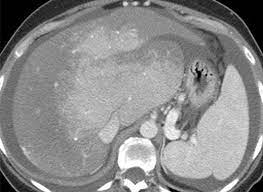

Chiasmata -mə-tə or chiasmas also chiasms 1. Esophageal varices are extremely dilated sub-mucosal veins in the lower third of the esophagus. Located in metro Denver northern Colorado and western Nebraska serving all of the Front Range our team consists of board-certified and fellowship-trained interventional radiologists. This results in hepatic congestion similar to Budd-Chiari syndrome and post-sinusoidal portal hypertension. The patients condition should be monitored throughout the procedure. They are most often a consequence of portal hypertension commonly due to cirrhosis. Toxic injury to liver sinusoids causes sloughing of endothelial cells that embolize to hepatic venules and cause eventual fibrosis of the venules. Coin in the Esophagus. There is no clear consensus regarding the number of occluded veins some authors claim that there should be at least one occluded hepatic vein 7 others state that there are no significant.

Carcinoma of the Colon. Budd-Chiari syndrome a blockage in one or more veins that carry blood from the liver back to the heart. And coumarin skin necrosis adrenal gland hemorrhage and infarction. Toxic injury to liver sinusoids causes sloughing of endothelial cells that embolize to hepatic venules and cause eventual fibrosis of the venules. Chiari malformation CM is a structural defect in the cerebellum characterized by a downward displacement of one or both cerebellar tonsils through the foramen magnum the opening at the base of the skull. Embolism and thrombosis of. La présence dune ou plusieurs affections prothrombotiques est fréquente La prise en charge repose sur un traitement anticoagulant précoce le traitement de l.